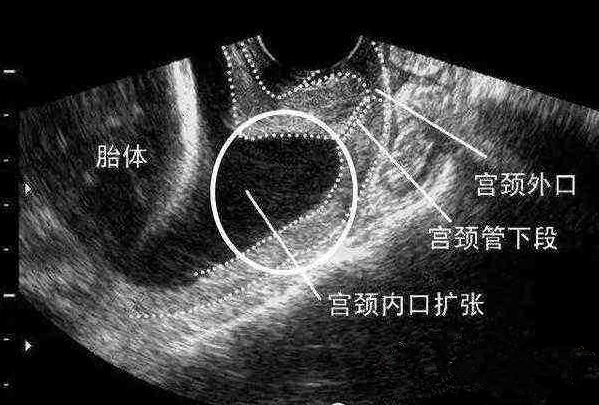

子宮與陰道之間的通道。上連子宮,下接陰道,呈現圓錐體的形狀,胎兒如果到了預產的時間,也是通過子宮頸管產出的。

宮頸管的長短,被當作是衡量胎兒早產與否的重要依據。宮頸管越短,那么胎兒早產的風險就越高。

如果宮頸管長度短于25毫米,就要警惕早產了。